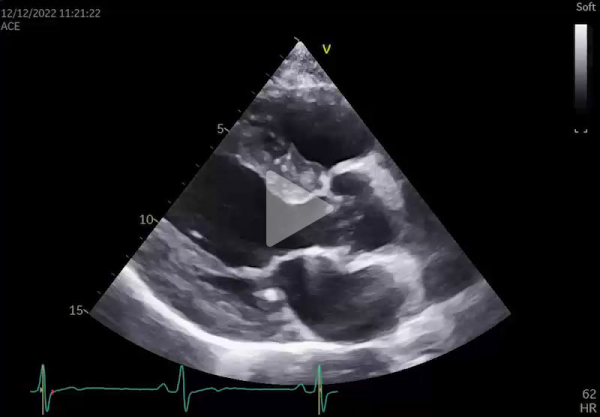

Une échographie cardiaque est demandée dans le bilan étiologique et devant l’aspect ECG (Vidéos 1 et 2, et Figure 2):

Vidéo 1 - Coupe parasternale grand axe (ETT)

L’échographie cardiaque montre:

- Hypertrophie circonférentielle de 17 mm (Figure 6)

- Diminution du strain de la paroi postéro-latérale évocatrice d’une maladie de Fabry sans élément pour une amylose (notamment pas de gradient base-apex) (Figure 2)

- Dilatation à 44 mm du sinus de Valsalva

- Remodelage VG concentrique ou HVG sans obstruction intra-VG à l’état de base

- Hypo- voire akinésie de la paroi inféro-latérale du VG (en rapport avec la fibrose) et altération du strain, particulièrement au niveau du segment inféro-latéral

- Aspect épaissi, infiltré des valves mitrale et aortique, avec régurgitation légère à modérée

- Hypertrophie du VD et des muscles papillaires

- Dilatation légère à modérée du sinus de Valsalva et de l’aorte ascendante dans les formes avancées de la maladie.